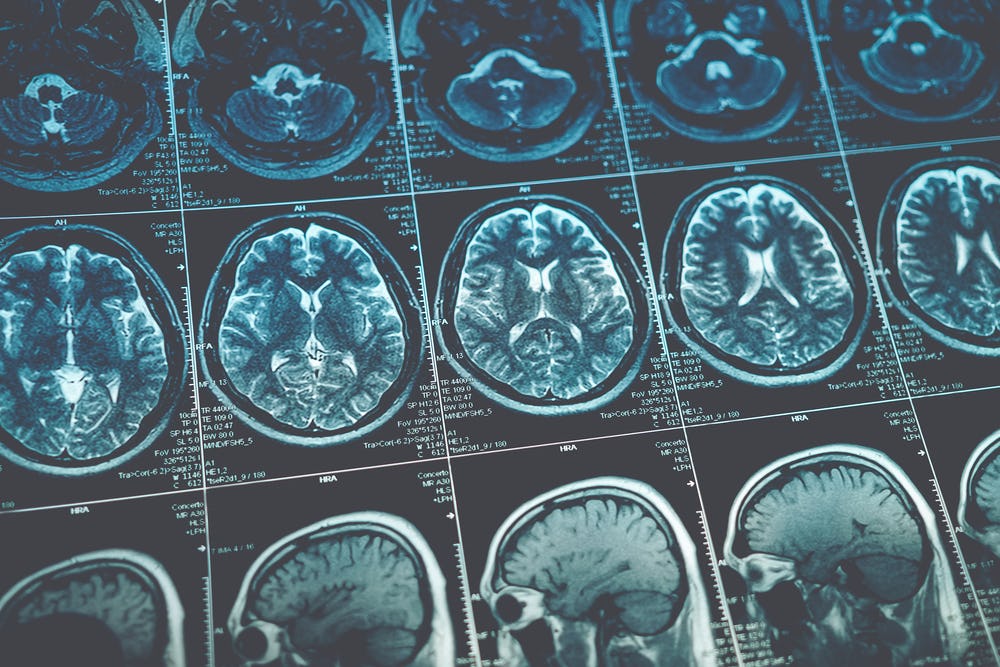

In the UK, a study found that around one in seven people surveyed reported having symptoms that included cognitive difficulties 12 weeks after a positive Covid-19 test. And a recent brain imaging study found that even mild Covid-19 can cause the brain to shrink. Only 15 of the 401 people in the study had been hospitalized.

The participants underwent detailed computerized cognitive tests an average of six months after their acute illness using the Cognition platform. This assessment platform is designed to precisely measure different aspects of mental faculties such as memory, attention, and reasoning and had been used in the above-mentioned citizen science study.